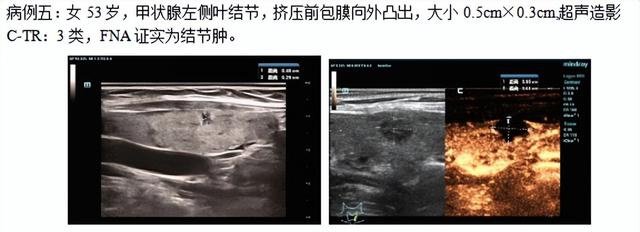

近期,石门县中医医院介入超声门诊成功开展甲状腺射频消融术6台(2例良性、4例甲状腺微小乳头状癌),术中、术后行超声造影检查,肿瘤消融完全患者总住院天数为2天,微创、无痛、并发症小、后期恢复快。

消融病例